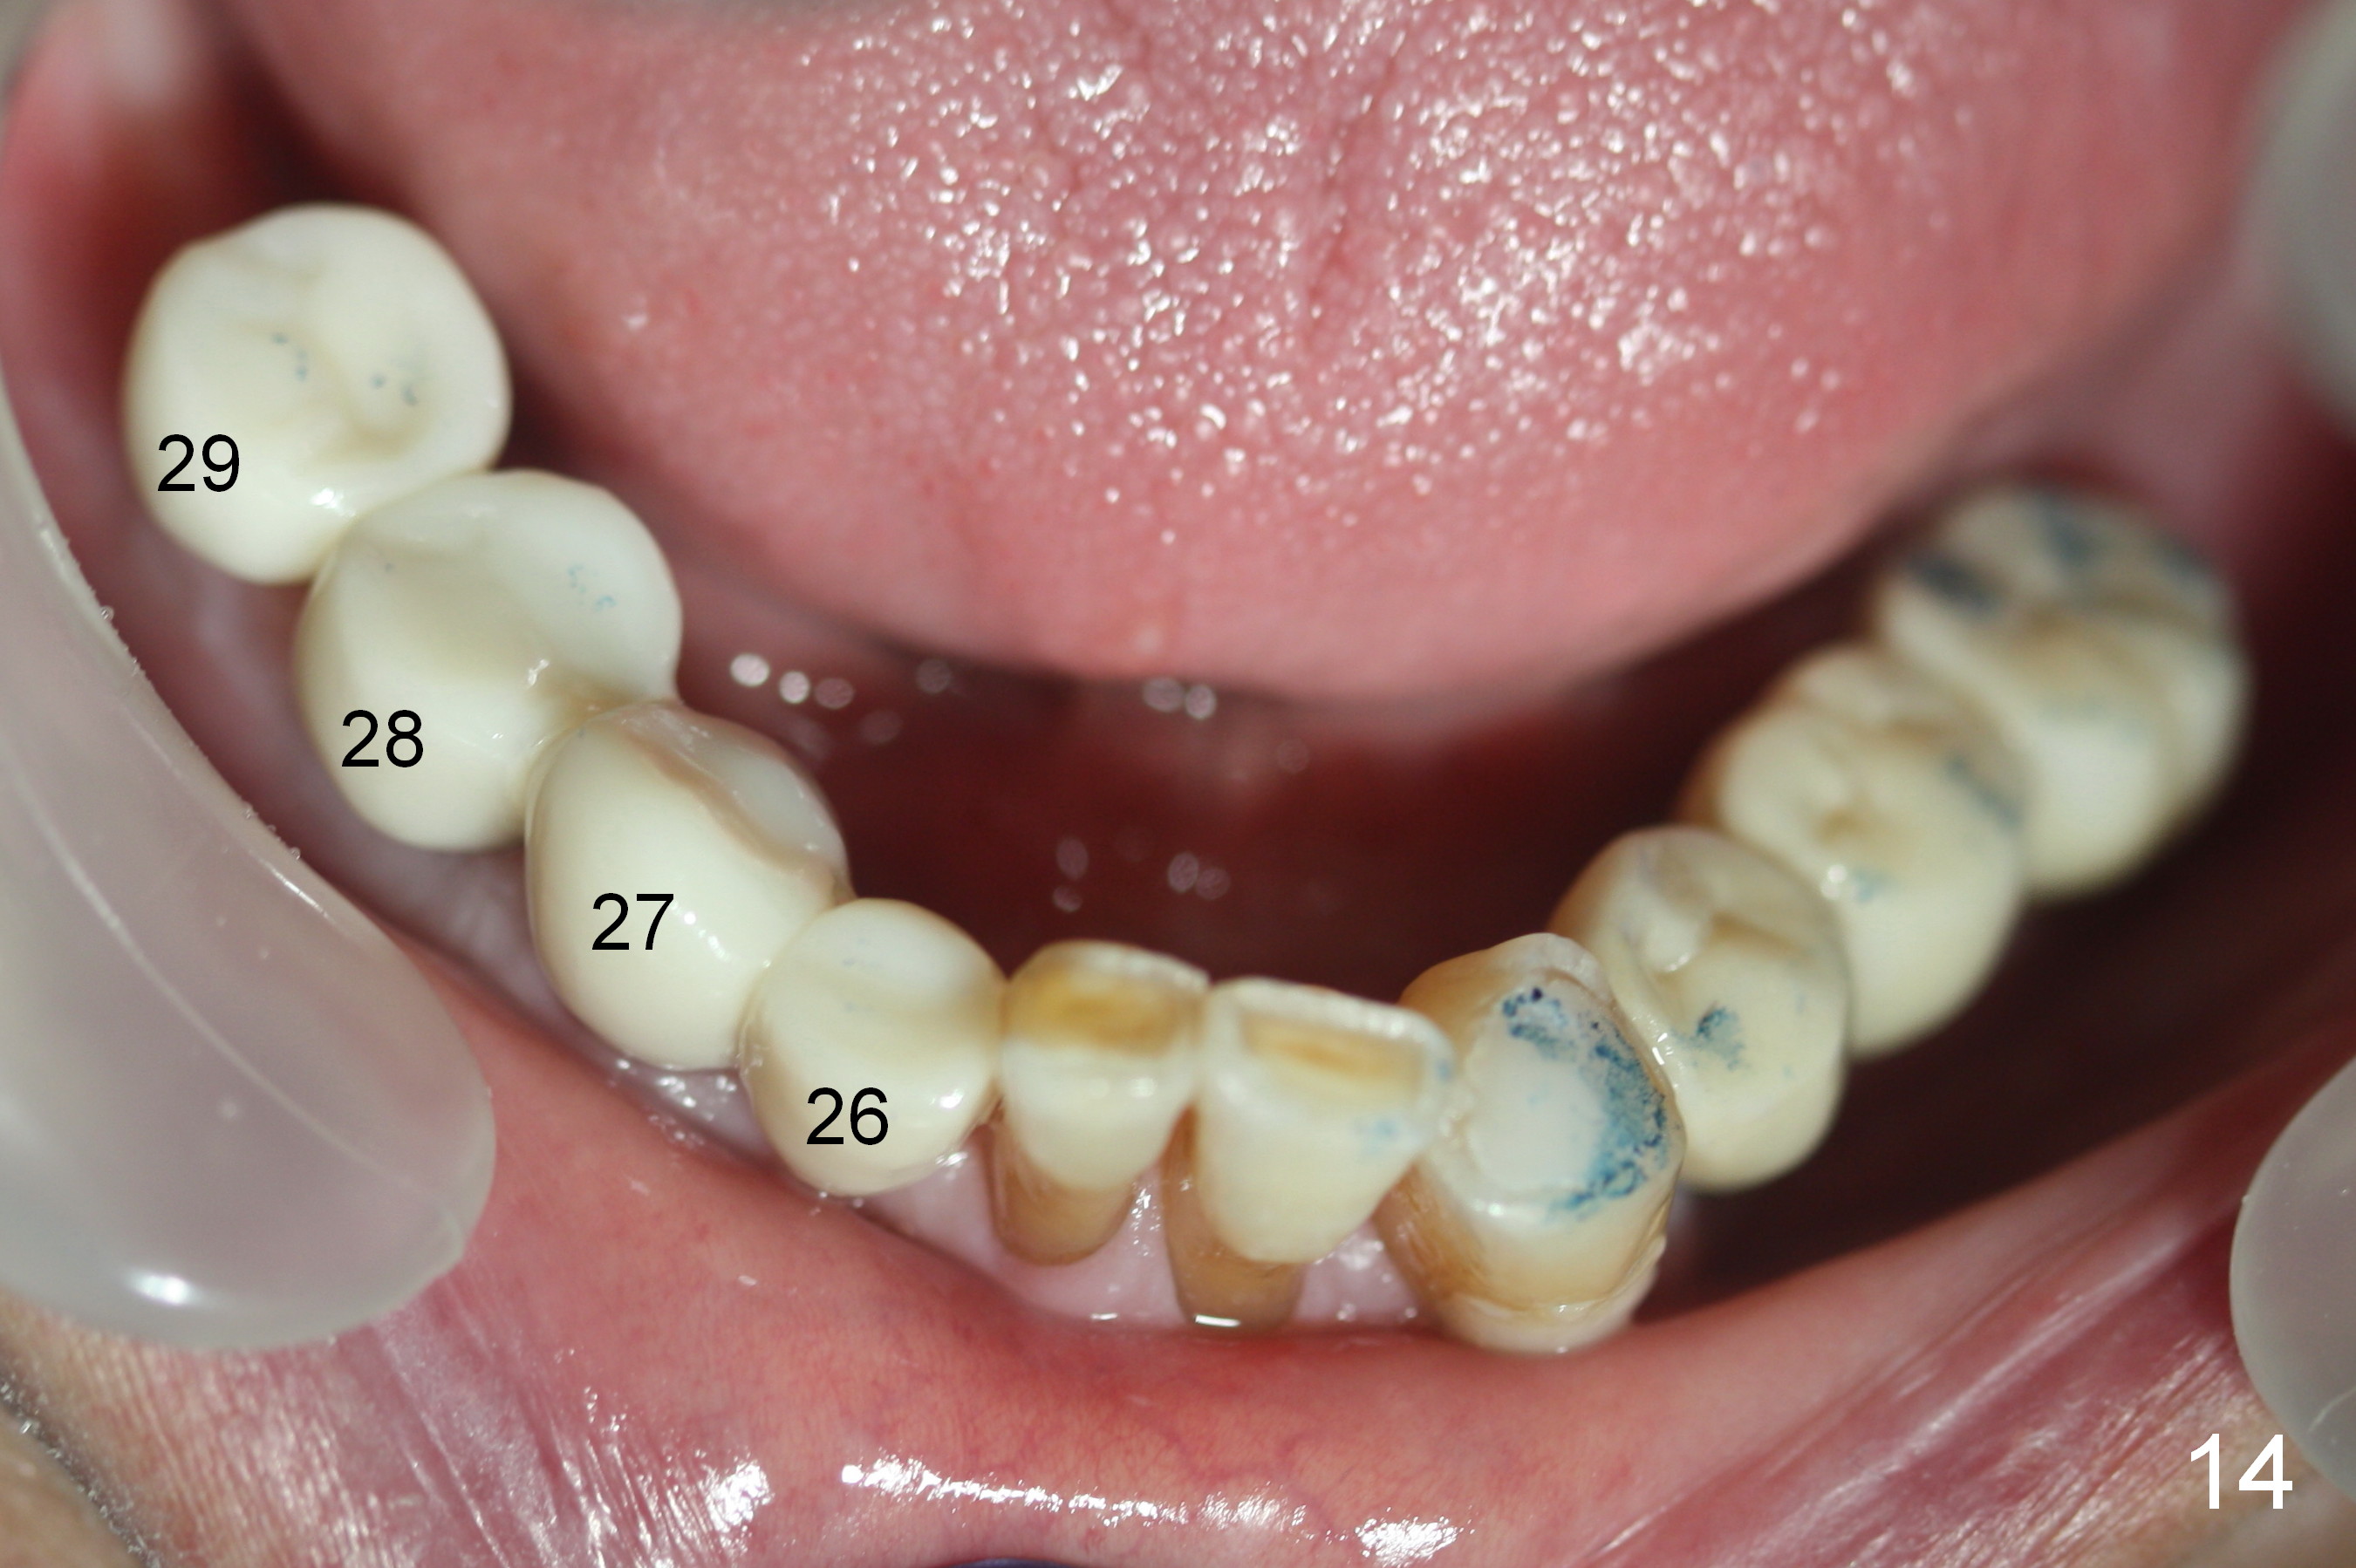

In fact, the crowns are splinted between #26-28, while the one at #29 is single unit (Fig.14). The patient is concerned that the bite on the lower right side is not strong. The occlusion for the most distal crowns should be tight.